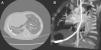

Caso 2Niña de 11 años derivada a nuestro centro para valoración por cardiología con diagnóstico neonatal de síndrome de la cimitarra (drenaje venoso pulmonar anómalo parcial a vena cava inferior y venas suprahepáticas, hipoplasia de pulmón derecho y arteria pulmonar derecha, secuestro extralobar). Asintomática hasta la fecha con buen desarrollo pondoestatural. Se realiza estudio angiográfico que confirma la presencia de una arteria de pequeño calibre proveniente de la aorta descendente a nivel de D12, que irriga el segmento posterior del lóbulo inferior derecho. Se constata durante el procedimiento hipertensión pulmonar leve (presión media de la arteria pulmonar de 28mmHg), por lo que se decide oclusión de la colateral arterial para el consiguiente descenso de la presión pulmonar. Se procede a la embolización mediante el uso de un coil de 3×5 seguido de un dispositivo oclusor tipo Amplatzer® de 4mm y otro de 8mm, lográndose oclusión completa sin incidencias (fig. 2).

Embolización endovascular de colateral aórtico-pulmonar. A: Imagen angiográfica de aorta descendente, donde puede observarse el nacimiento del vaso nutricio del SP (colateral aórtico-pulmonar). B: Acceso a la arteria colateral aórtico-pulmonar que irriga el SP. C: Embolización de la colateral mediante un coil y 2 tapones vasculares tipo Amplatzer®. D: Comprobación de la oclusión completa del vaso nutricio tras la embolización.